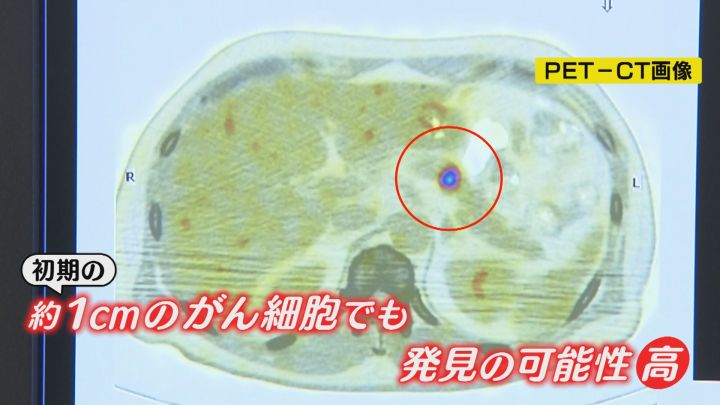

「ここ光っていますよね。ここがすい臓がん。CTではわからないんです。大きさとしては1.5センチくらいなんですが、他の周りのリンパ腺とかにも転移がないし、この方は手術で救命ということです」

「初期」に当たる1センチ程度の小さながん細胞でも発見できる可能性が高いということです。

「PETの検査は早いうちから、小さなうちから所見が出る。早く見つければがんは怖い病気でも何でもない」

“沈黙の臓器” と言われる、すい臓がんでも同様です。

「背中が痛いと言ったときはもう、背中の骨に転移している状況で見つかることが多いので、早期に見つけるのが非常に難しい場所。うちも数年に一人くらいは早期のすい臓がんを見つけている」